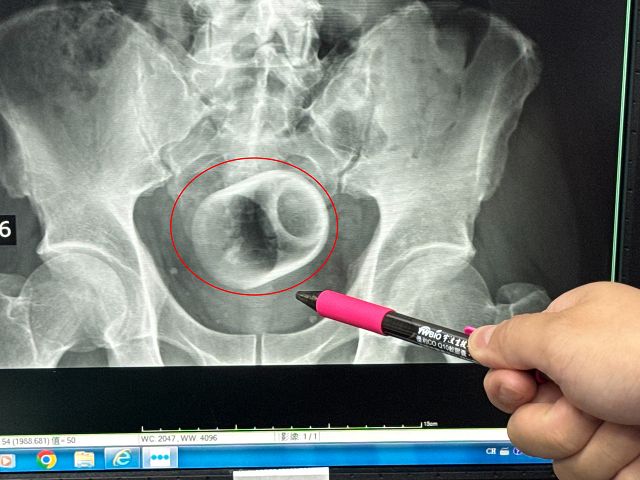

中部一名男子腹脹三天無法大便,肚子痛到受不了,趕緊到醫院求診,經過X光檢查,醫師驚見患者的肛門竟然塞一個直徑約6公分、高約8公分的陶瓷杯,外科醫師原本要使用器械把杯子夾出來,但杯緣光滑無法施力,杯子全被大腸包住,部分腸子缺血也造成壞死,最後全身麻醉「開腸破肚」的才把杯子取出。

駐診在李綜合醫院的台中榮總外科醫師吳坤達表示,該名患者到院時,自訴三天無法大便非常困擾,害羞不敢提及自己肛門塞了一個杯子,經過X光攝影,看到骨盆腔內有一個杯子,杯口朝下,因此,馬上安排進手術室,要把杯子拿出來。

吳坤達說,一開始試著使用器械直接把杯子夾出來,但是杯子光滑,用了很多器械,試了很多次都無法成功,後來再使用腹腔鏡,依舊無法順利取出,擔心把杯子夾碎,傷及患者或造成感染風險,最後只好在肚子上動刀,直接「破肚開腸」劃開腸子,總共花了兩個多小時,才順利取出杯子,同時做了一個人工造口,讓患者能夠暫時解便。